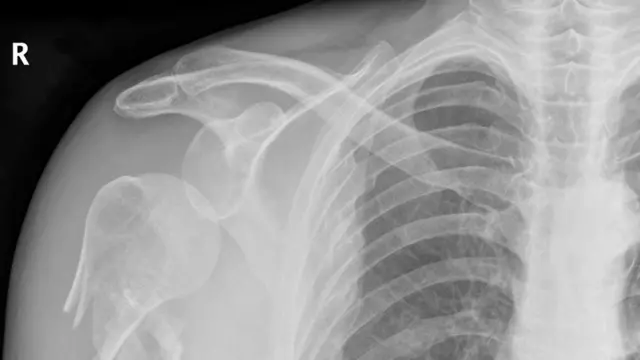

Esta característica significa que podría utilizarse como un nuevo tipo de rayos x capaz de obtener imágenes de una resolución mucho mayor que la alcanzada hasta el momento con los rayos x convencionales.

Una de las aplicaciones prácticas más evidentes es en el campo de la medicina: la luz podría por ejemplo utilizarse para detectar microfracturas.